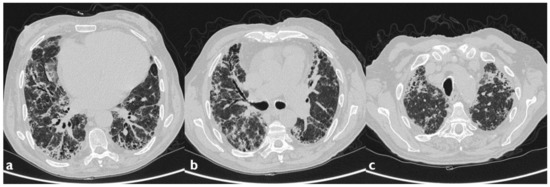

| HRCT Pattern | Associated Drugs |

|---|---|

| Fibrotic pattern | Nitrofurantoin (chronic toxicity), methotrexate, sulfalazina, rituximab, tocilizumab, bleomycin, busulfan, cyclophosphamide (chronic toxicity), amiodarone (form with fibrous course), tocainide, cocaine |

| Organizing pneumonia | Nitrofurantoin (chronic toxicity), methotrexate |

| Mosaic pattern | Nitrofurantoin (acute toxicity), methotrexate, sulfalazina |

| Isolated ground glass | Rituximab, tocilizumab, cyclophosphamide (acute reaction), amiodarone (initial stage), cocaine |

| Alveolar hemorrhage | Penicillamine, rituximab, cocaine |

| Pulmonary edema | Acetyl-salicylic acid, mitomycin |

| Pleural effusion | Sulfonamides, methotrexate |